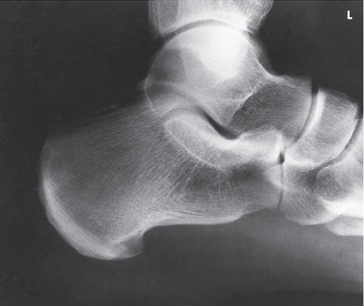

Name this projection.

Lateral calcaneus

What type of projection is it?

Mediolateral

Is the patient on the affected or unaffected side?

Affected

State specifically where the CR enters.

Perpendicular to the calcaneus // 1" distal to the medial malleolus

Which tarsal is in profile?

Calcaneus

Which radiographically significant landmark is open?

Sinus tarsi